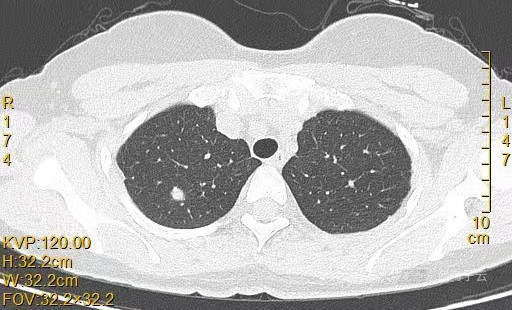

患者女,44岁,无特殊症状,做体检时发现右肺结节。查到1年前的体检CT片,右上肺当时就有一个直径约3mm的微小结节。两次检查检查图片如下:

以下三张为1年前CT片:

以下9张为今年5.10的CT图片: